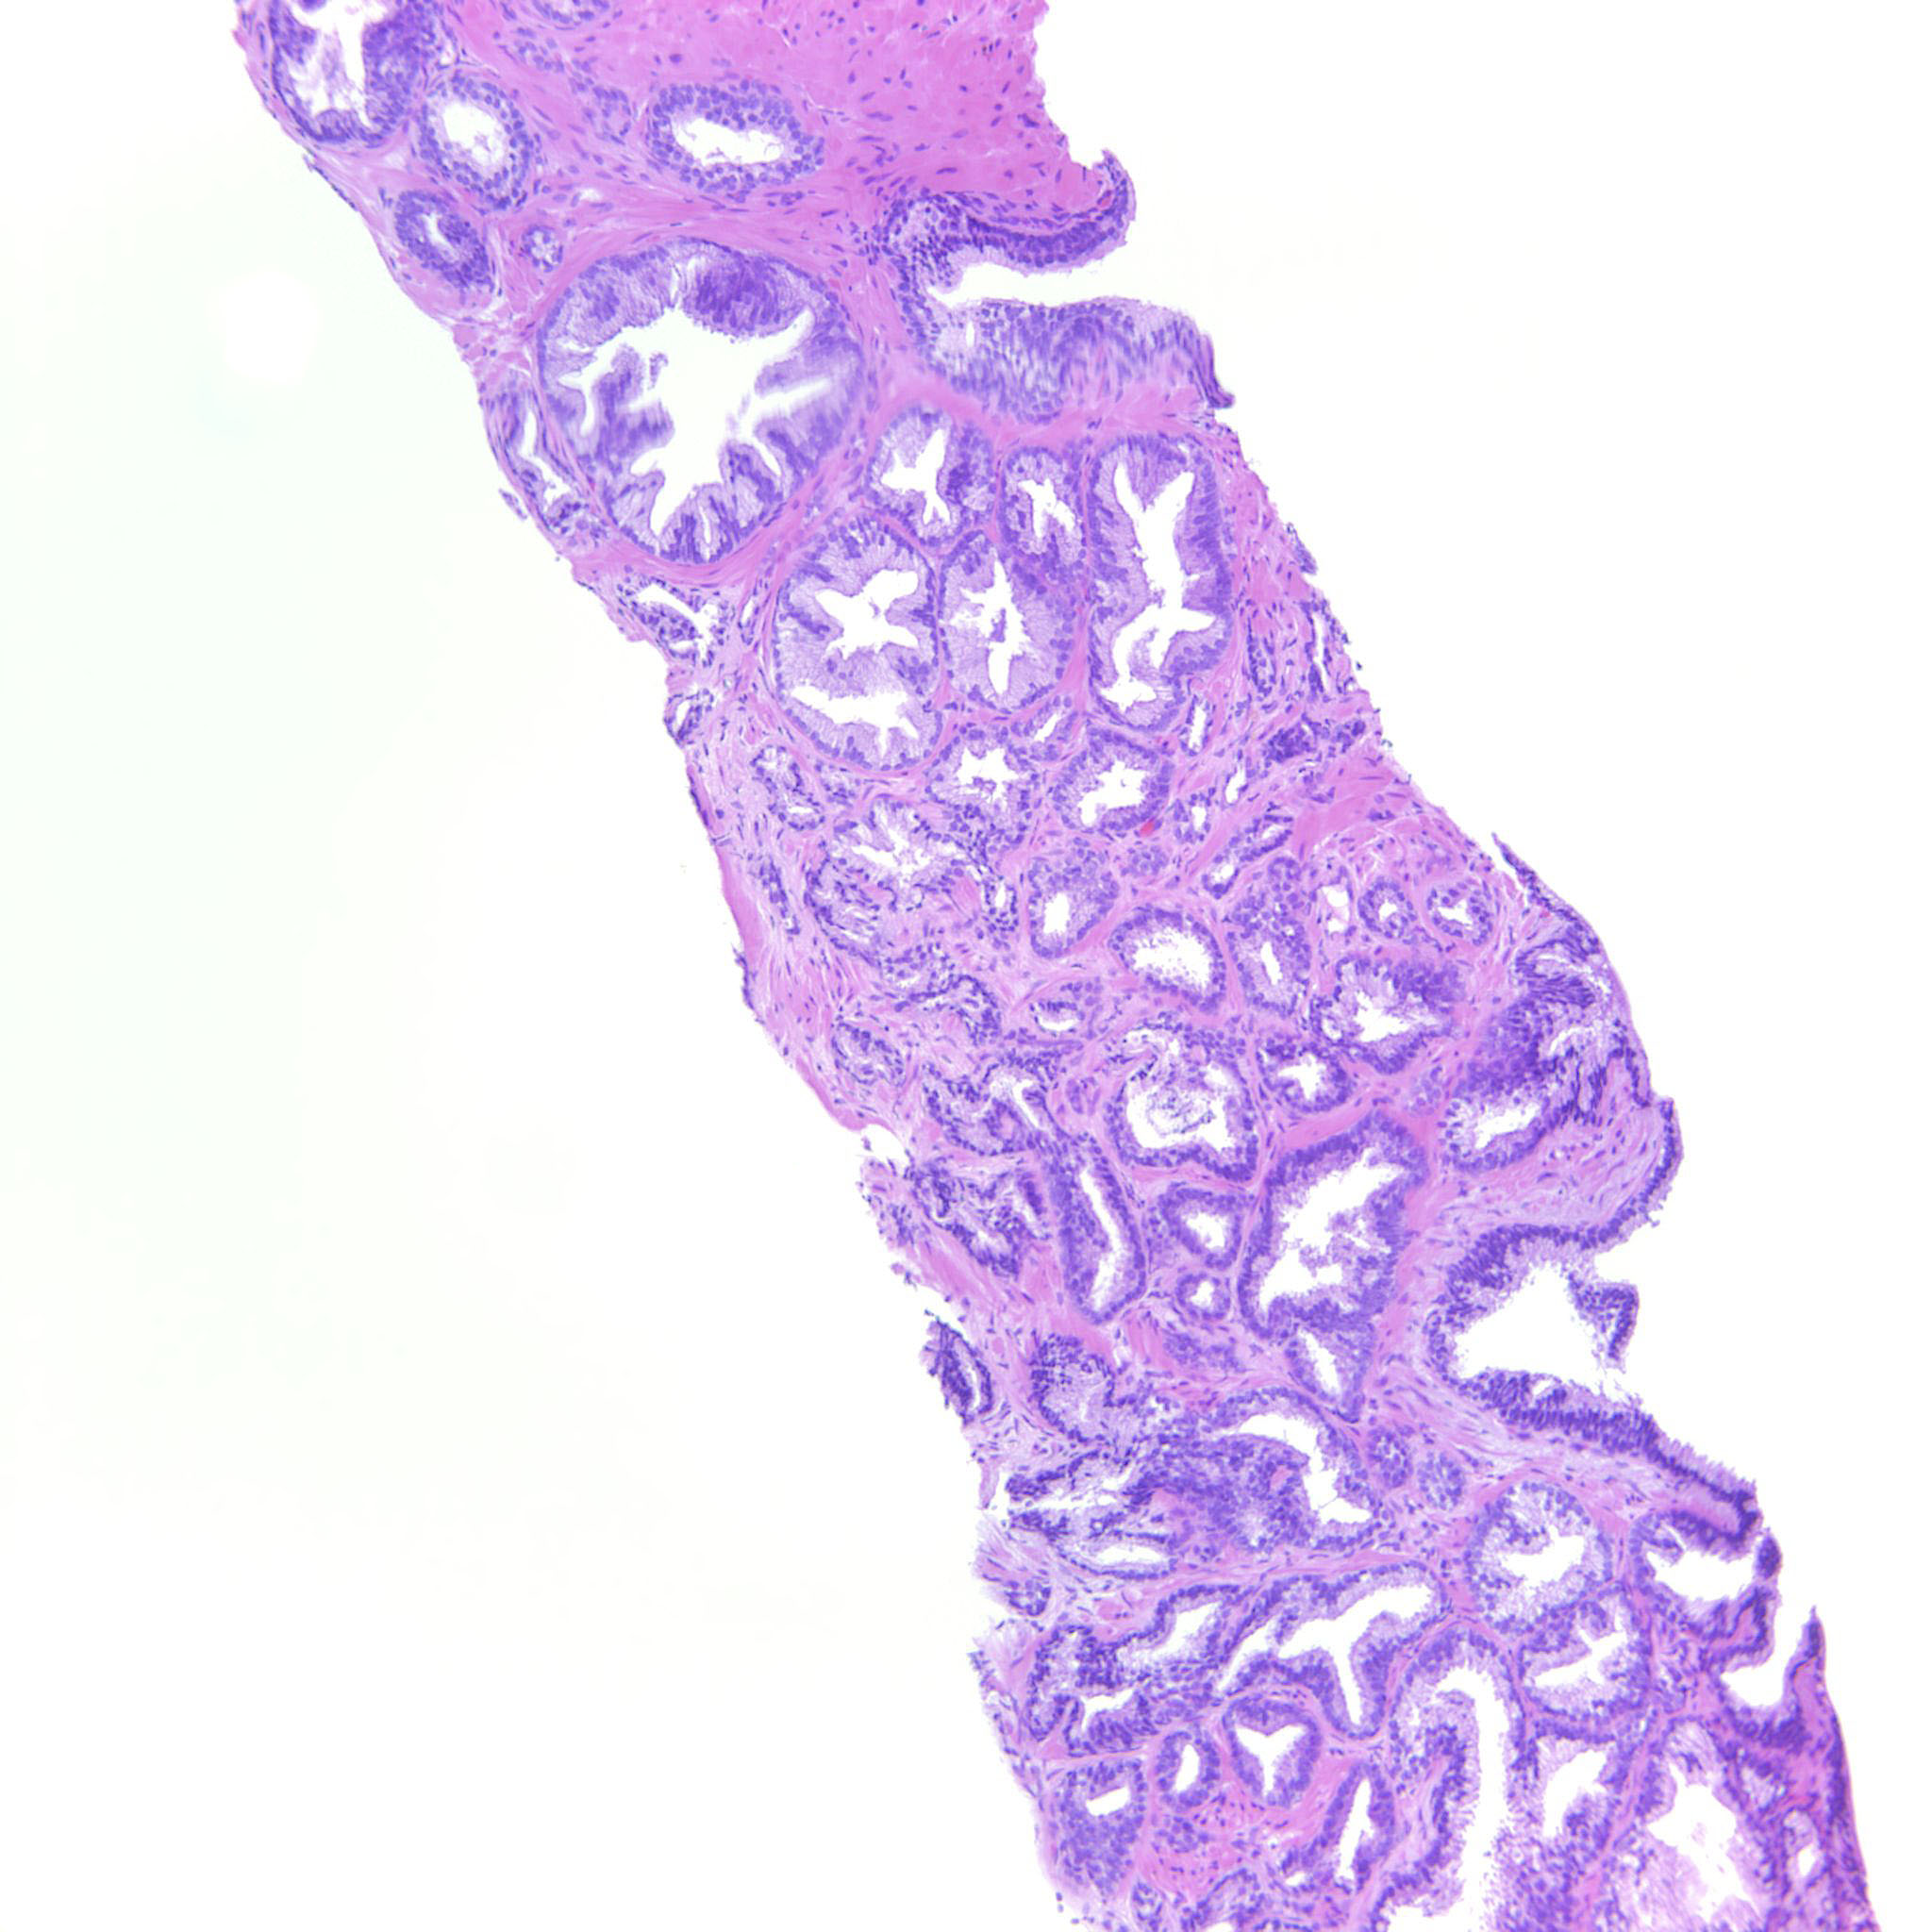

Prostate cancer grading

Case ID: 314